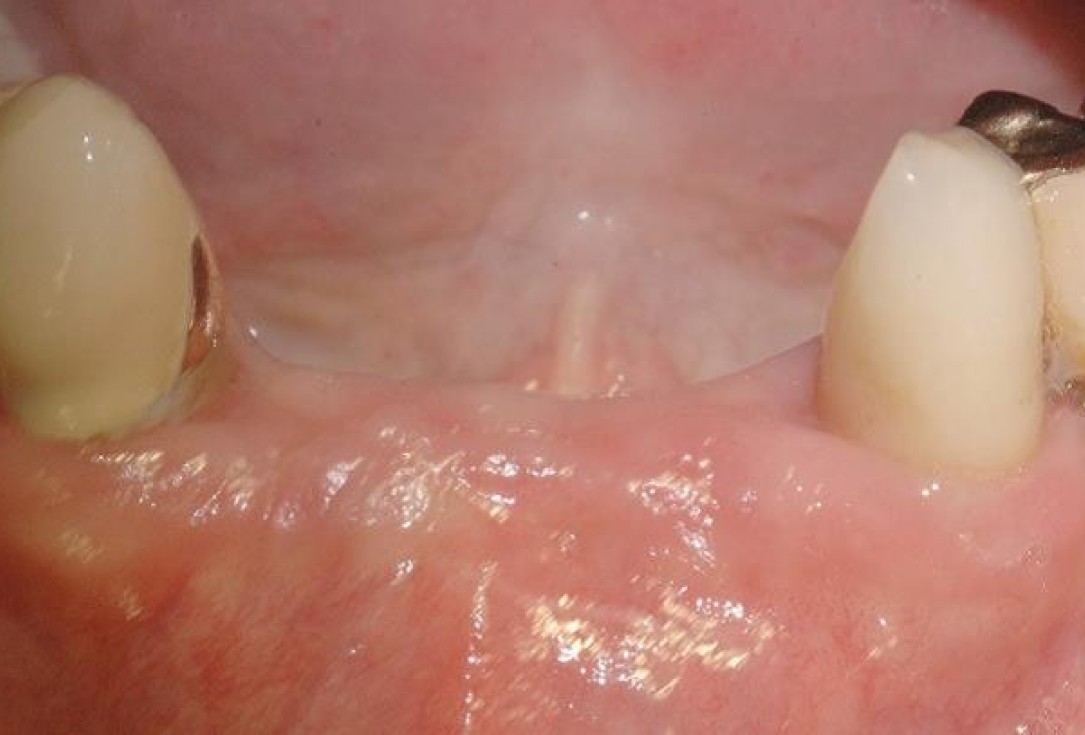

2/15 - 3 months after extraction visible bone and soft tissue loss in regio 42-32Soft tissue augmentation and GBR with mucoderm® and maxresorb® - Dr. S. Scherg